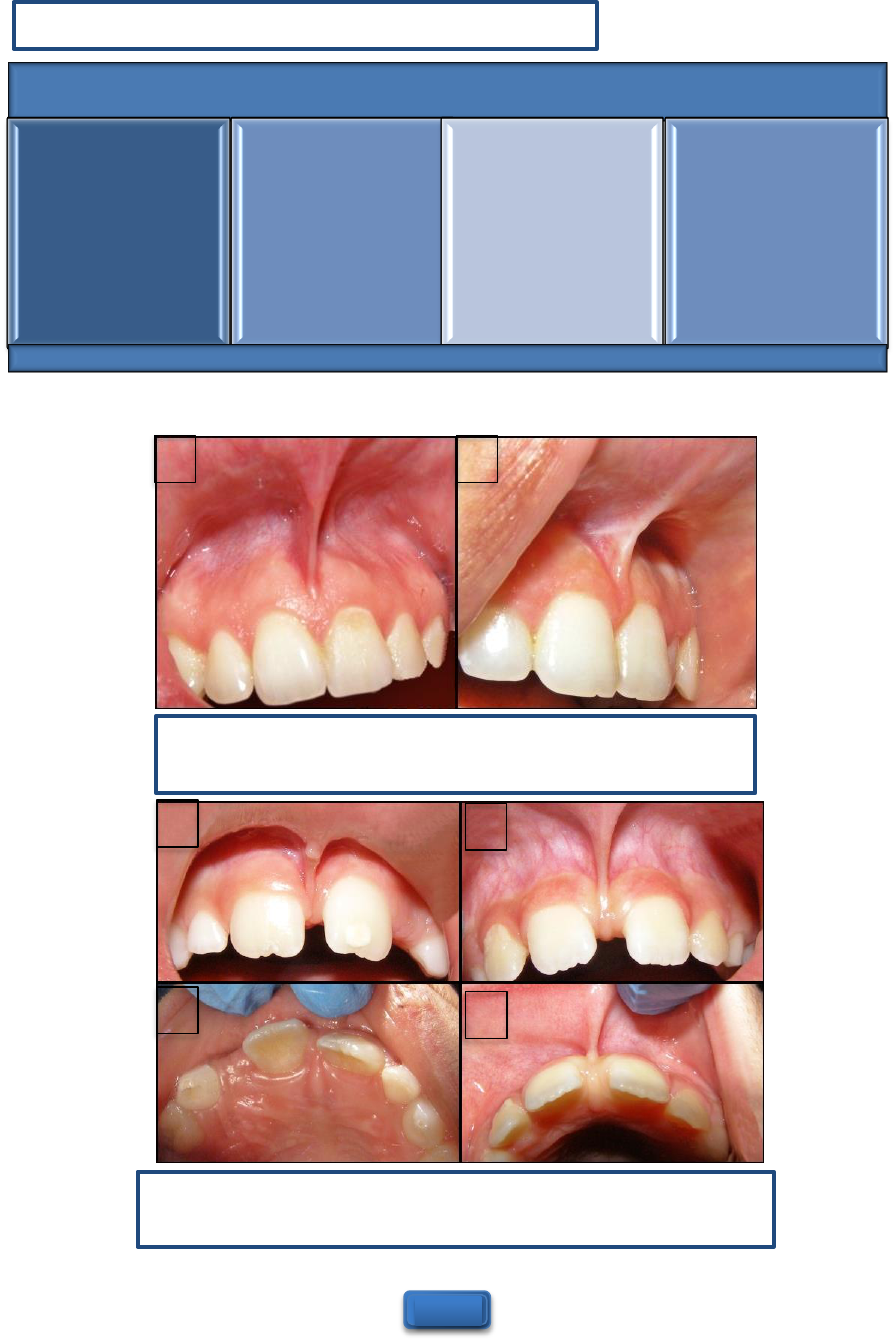

freio labialfreio superiorfreio emfreio bebefreio Freiofreio lingual:freio TUDOfreio ofreio quefreio vocêfreio precisafreio saberfreio sobrefreio ofreio assunto!freio FRENECTOMIAfreio Grátis:freio FREIOS